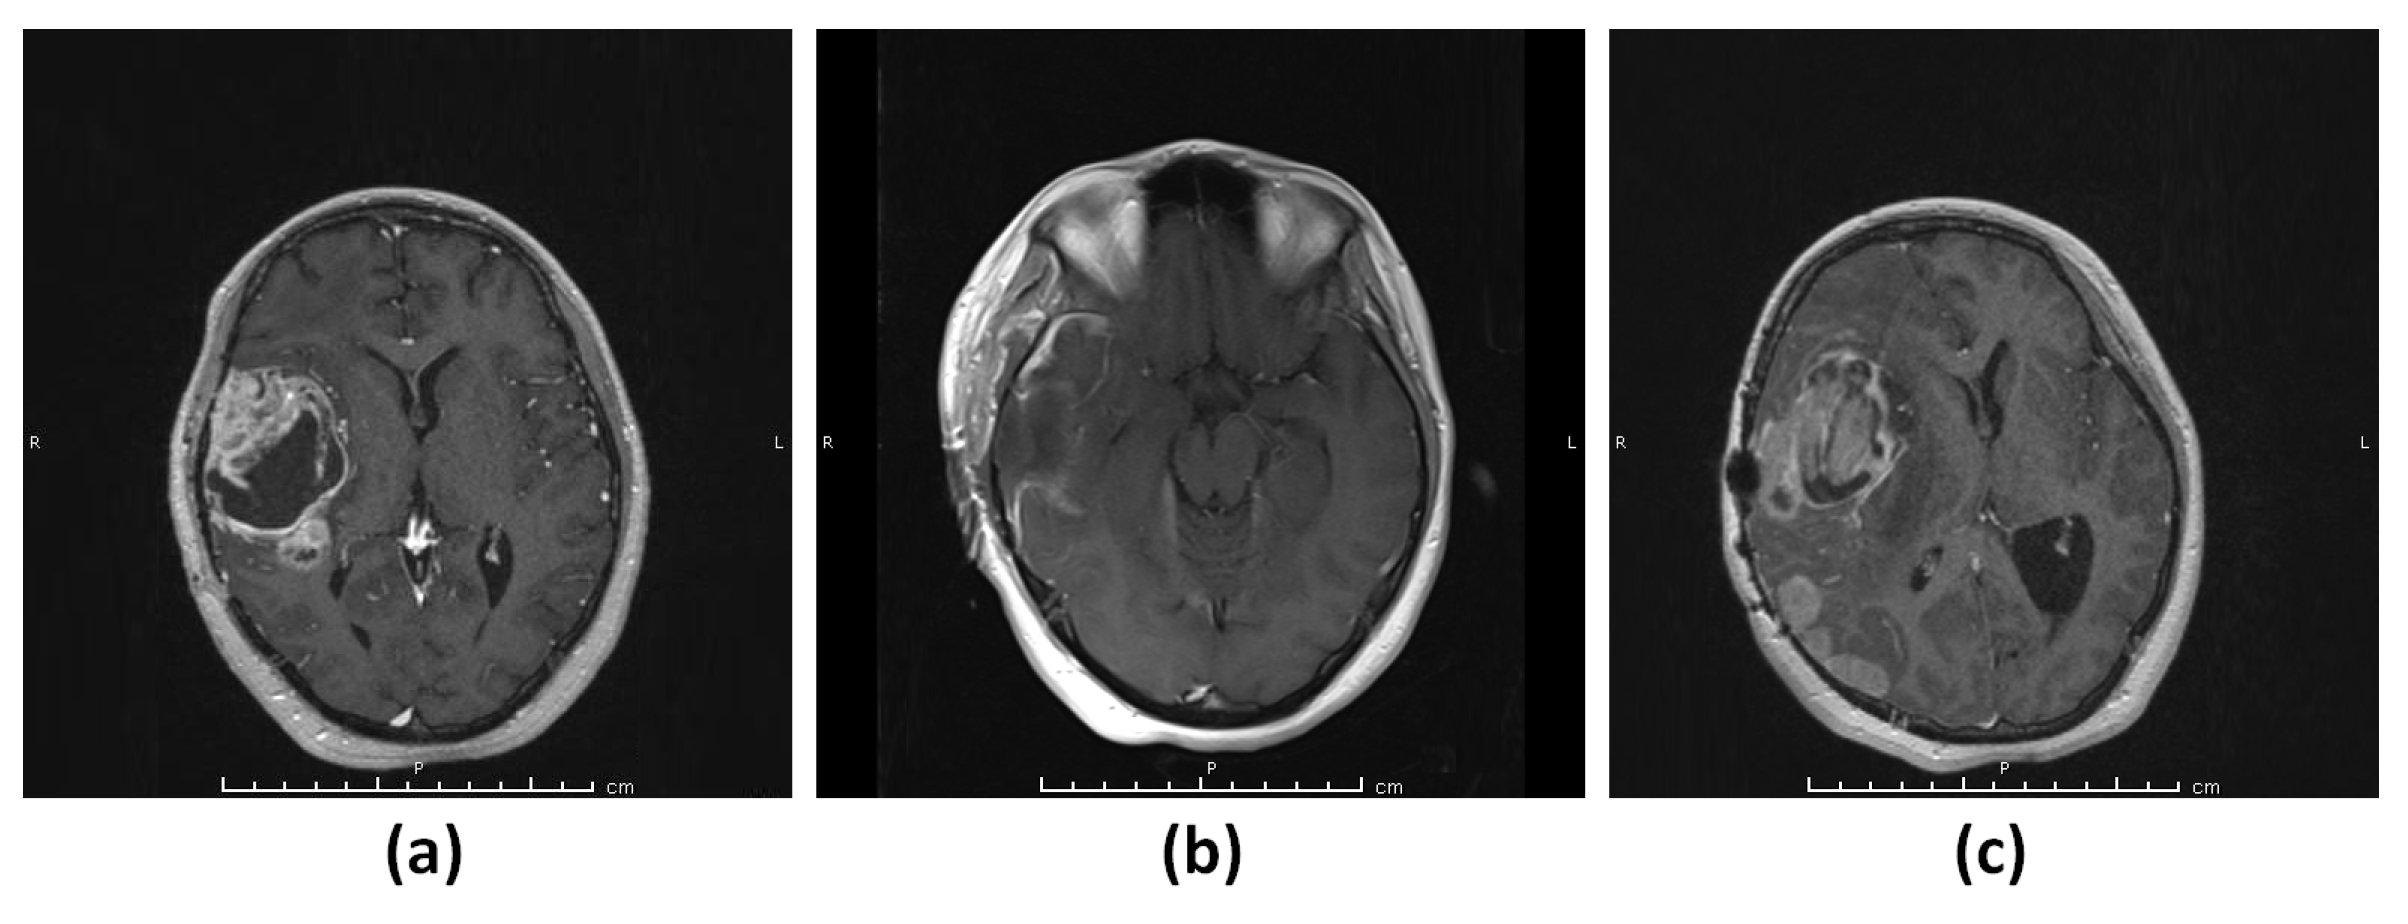

3.1.1. Patient 1 (G1)

3.1.2. Patient 2 (G2)

3.1.3. Patient 3 (G3–4)